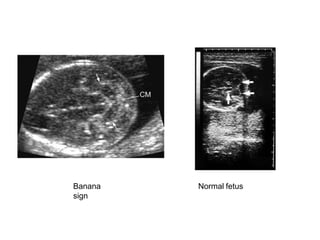

Banana

sign

Normal fetus

Chiari IISupratentorial

pathology• Luckenschadel or Lacunar skull

– result of abnormal radial growth of the skull, seen in upto 85% of

cases

– Focal areas of cortical thinning and scalloped appearance of the

skull

– most prominent at birth, may resolve with age

– not a result of raised ICP and hydrocephalus